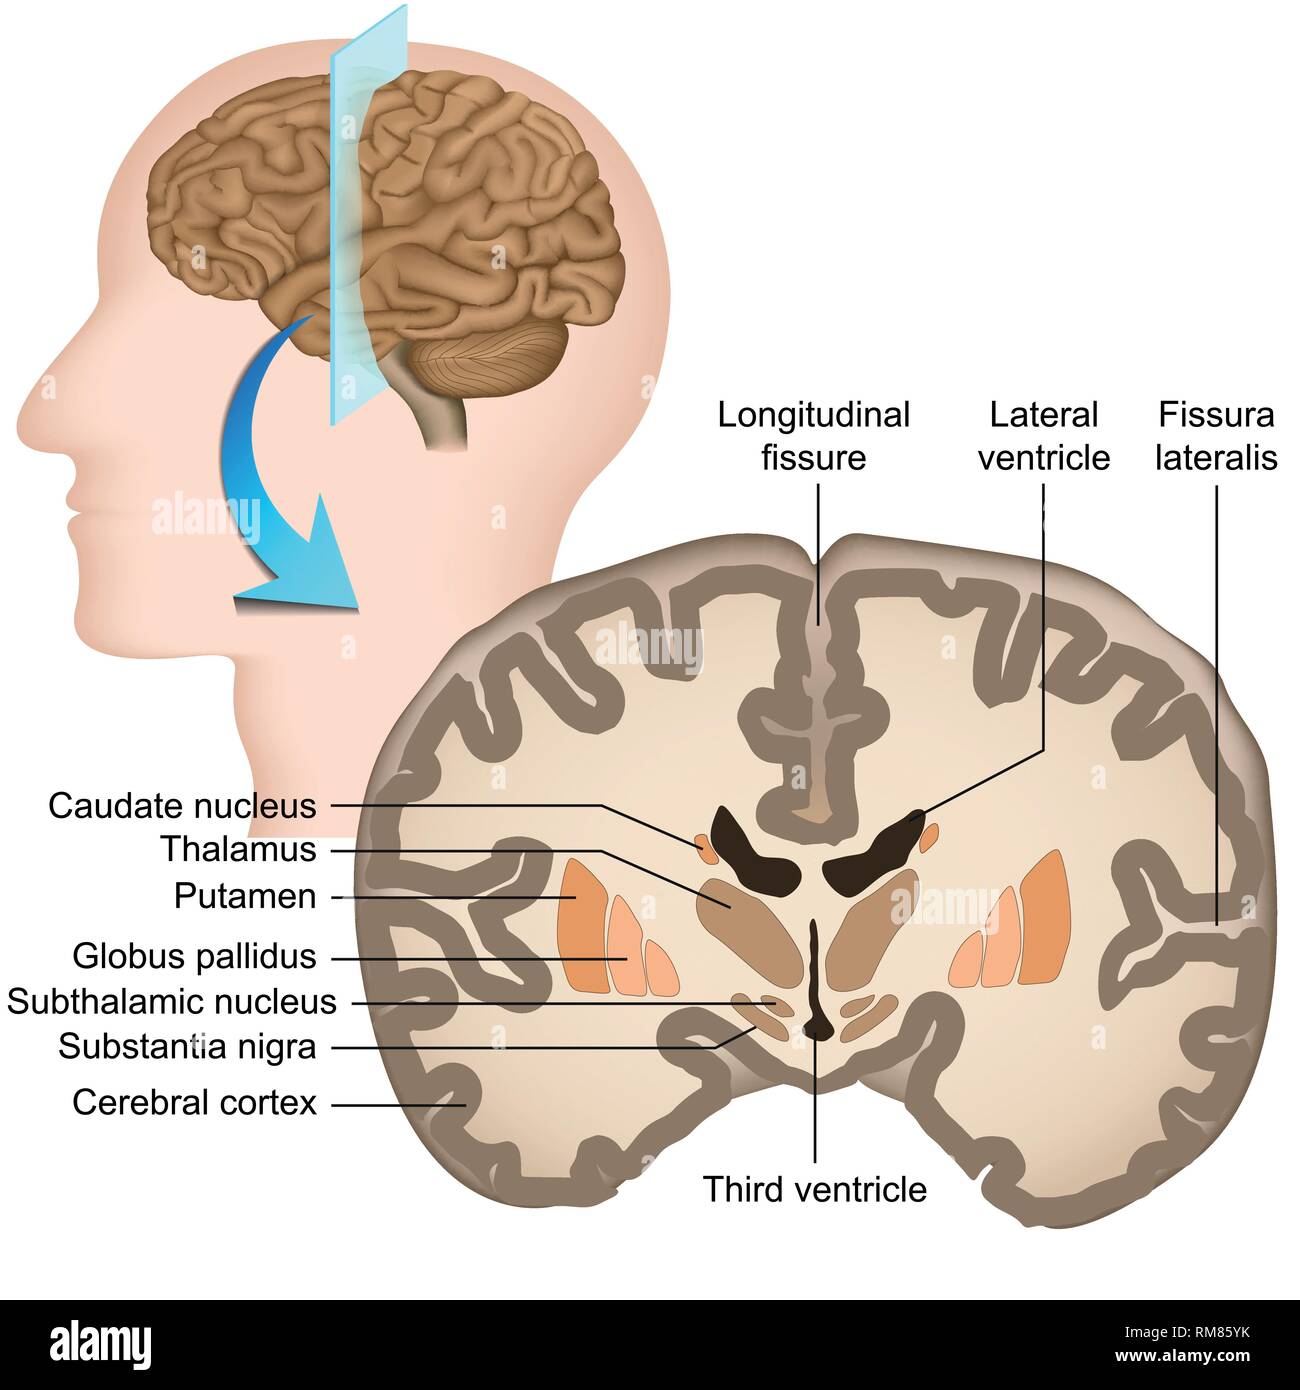

RF3CPM9D1–Abbildung des menschlichen Gehirns mit farbigen Ventrikeln: Lateral (gelb), dritter (orange), vierter (blau), interventrikuläres Foramen (grün), cerebral

RF3CPM9CD–Abbildung des menschlichen Gehirns mit farbigen Ventrikeln: Lateral (gelb), dritter (orange), vierter (blau), interventrikuläres Foramen (grün), cerebral